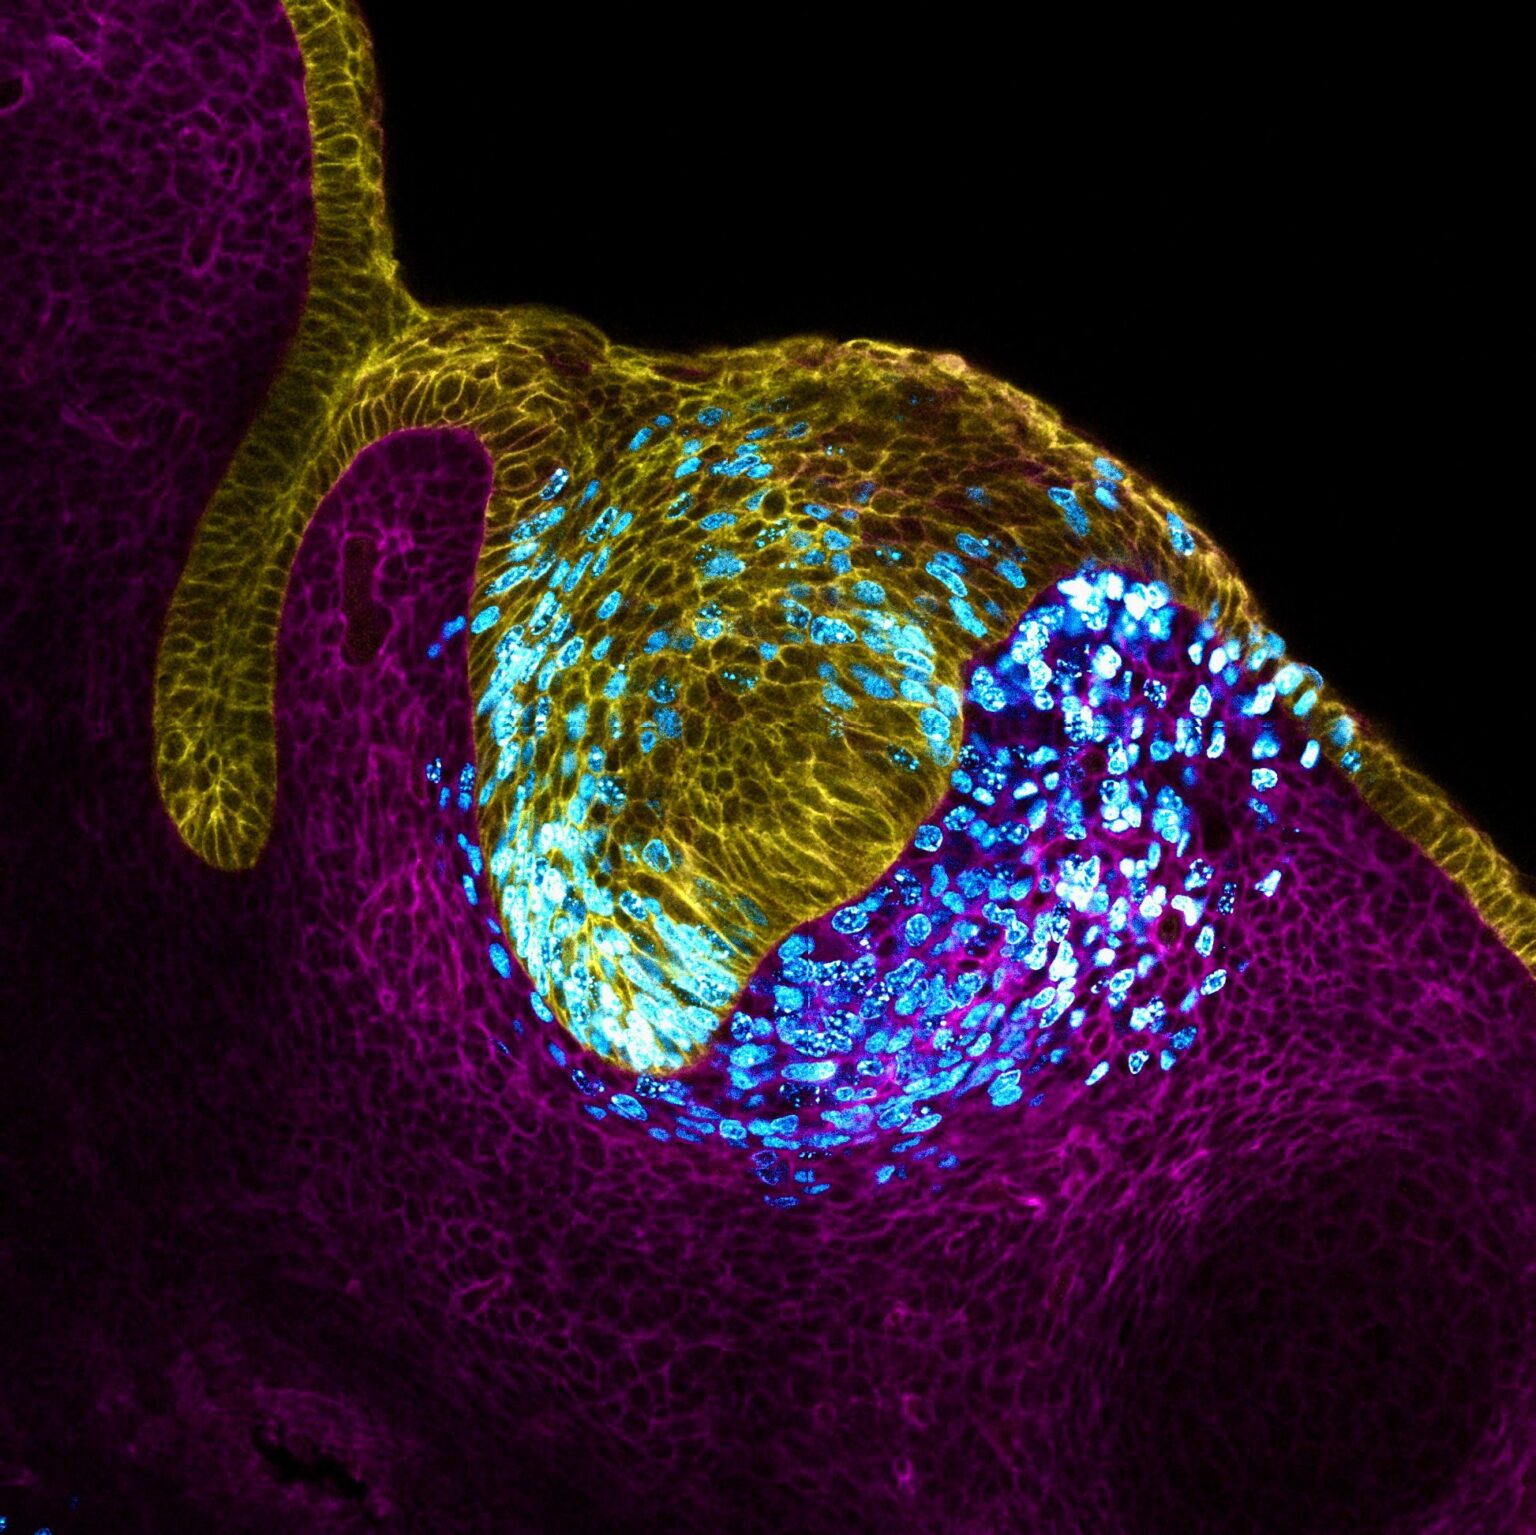

Organ development is a complex and intricate process that involves the coordinated differentiation, morphogenesis, and maturation of diverse populations of cells into functional organs. This process is orchestrated by dynamic gradients and combinations of growth factors, and requires long-term culture and postprocessing or maturation of naive tissues after cell seeding. Fortunately, engineering advances have enabled us to recreate various aspects of organ development in vitro, including the use of materials with tunable properties, microfluidics-based organ systems or “organs-on-a-chip,” 3D organoids, and engineering complex tissues for whole organ replacement.

One of the most promising approaches to organ development is the use of organoids, which are 3D cellular structures that mimic the architecture and function of in vivo organs, in part or in toto. Organoids can be used to study the development of organs in a more physiologically relevant context, as they mimic the physical, chemical, and biological interactions in natural tissues at different scales, from molecules to cells to building blocks to organized clusters.